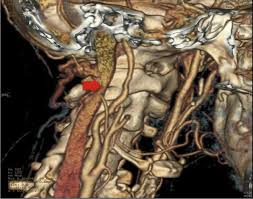

Blood in the separated layers of the vessel wall can lead to blood clot formation. A carotid dissection is a tear in the artery wall that allows blood to flow between the wall layers. It can manifest as headache (the most common early symptom (3)) with or. The tear may cause stenosis, an irregular narrowing of the opening in the vessel, and occlusion, a flap of the vessel wall protruding into the opening. Blood leaks out through this gap and spreads between the layers of the wall. Advertising on our site helps support our mission. Commonest in those in their mid 40s but seen at any age. Blood vessel walls normally have three layers, and a tear in any of these can allow blood to flow into the resulting space, causing the vessel to bulge.

Carotid artery dissection (concept id: Each common carotid artery has an internal and an external branch. Carotid artery dissection is a tear in one of the layers of the artery wall. Spontaneous dissection of the carotid artery occurs in 3 per 100,000 of the population annually (1). It manifests with headache, neck pain, temporary vision loss, and/or ischemic stroke. This causes bleeding into the artery wall. Commonest in those in their mid 40s but seen at any age. Roller coasters are also a no no. Blood vessel walls normally have three layers, and a tear in any of these can allow blood to flow into the resulting space, causing the vessel to bulge. The first portion of each carotid artery is the called the common carotid artery. Carotid artery dissection is a major cause of cerebral infarction in the young. Mr signal of the mural hematoma has a similar temporal evolution than intracerebral counterpart. A carotid dissection can be due to injury.

The natural history of cerebrovascular fmd is unknown and management of symptomatic patients can be challenging. A carotid dissection is a tear in the inner layer of the wall of a carotid artery that allows bleeding into the artery wall. Internal carotid artery (ica) dissection, like arterial dissection elsewhere, is a result of blood entering the media through a tear in the intima 1 and is a common cause of stroke in younger patients. Carotid artery dissection has been described after chiropractic manipulation. It can involve a carotid or vertebral artery and sometimes multiple arteries can be involved.